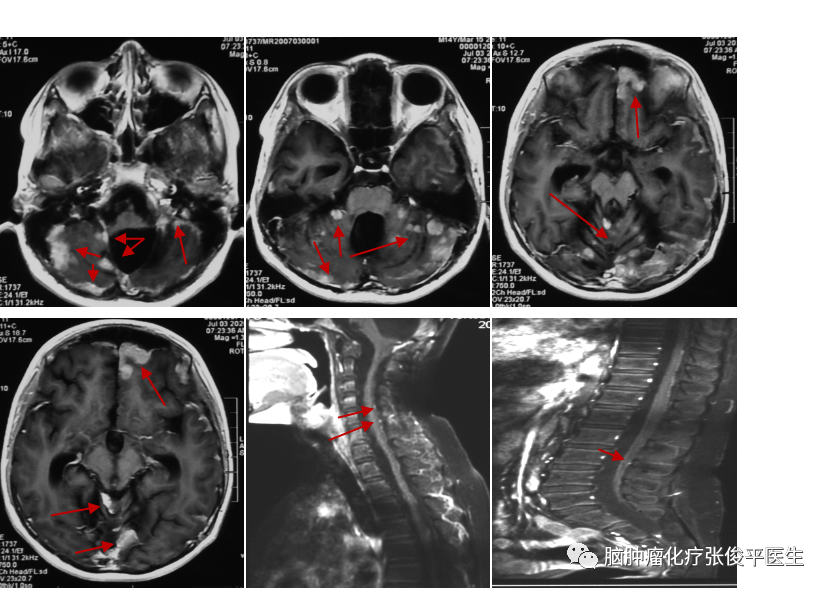

患者董**,男,14岁。2019年年初患者出现恶心呕吐,未重视。2019年4月患者出现头痛,遂行头部MRI示:双侧小脑半球、蚓部、四叠体区占位。患者于2019-4...